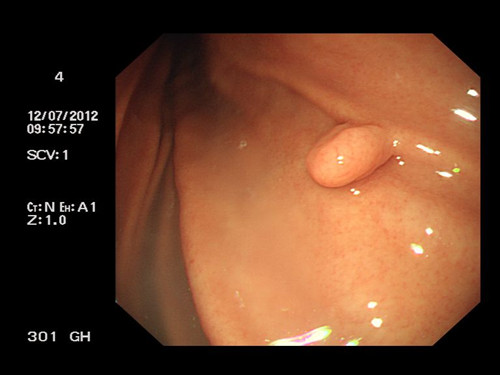

胃息肉癌變幾率有多大

胃息肉,是起源于胃黏膜上皮細(xì)胞凸入胃內(nèi)的隆起性病變。胃息肉較小時(shí)常無(wú)明顯癥狀,一般都是在胃腸鋇餐造影、胃鏡檢查或其他原因手術(shù)時(shí)偶然發(fā)現(xiàn)。我們知道,在胃癌的癌前病變中,就有胃息肉的一席地位。那么,胃息肉的癌變幾率到底有多大呢?

胃息肉是胃粘膜上皮或間質(zhì)成分增生所引起的息肉狀病變。胃息肉可分成非腫瘤性息肉(包括增生性息肉、錯(cuò)構(gòu)瘤性息肉、炎性息肉、異位性息肉等)和腫瘤性息肉(包括扁平腺瘤即管狀腺瘤和乳頭狀腺瘤即絨毛狀腺瘤)兩大類。

胃息肉癌變的癌變率與有無(wú)不典型增生有很大的關(guān)系。腺瘤性息肉有不同程度的不典型增生,其有三種病理類型:管狀腺瘤癌變率約10%、絨毛狀又稱乳頭狀腺瘤癌變率高達(dá)50%-70%、混合型腺瘤居于兩種之間。而增生性息肉屬于腺體增生延長(zhǎng),絕大多數(shù)無(wú)不典型增生,癌變率只有0.4%。

除了種類的不同,胃息肉癌變的幾率還受息肉體積大小、患者病程、生長(zhǎng)速度等因素影響。其中息肉體積的大小就是很重要的一個(gè)因素。胃息肉的大小一般都不到一厘米,只有很少數(shù)的人增生性息肉會(huì)引起不良反應(yīng),癌變的幾率也較低;息肉直徑大于2cm、廣基、多發(fā)性息肉癌病率較高;當(dāng)胃息肉直徑大于3cm時(shí),癌變率更是高達(dá)70%。

我們看到,雖然胃息肉不是胃癌,但是部分胃息肉有惡變的可能,是胃癌重要的癌前期狀態(tài)。對(duì)于胃癌的預(yù)防,胃息肉患者尤其需要重視。